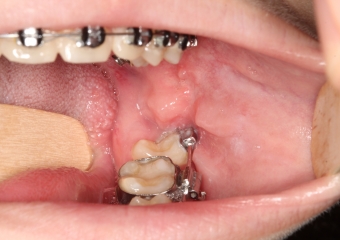

Extração dos 4 terceiros molares   - Instalação de placas de ancoragem - Clínica Cliniface

Extração dos 4 terceiros molares - Instalação de placas de ancoragem